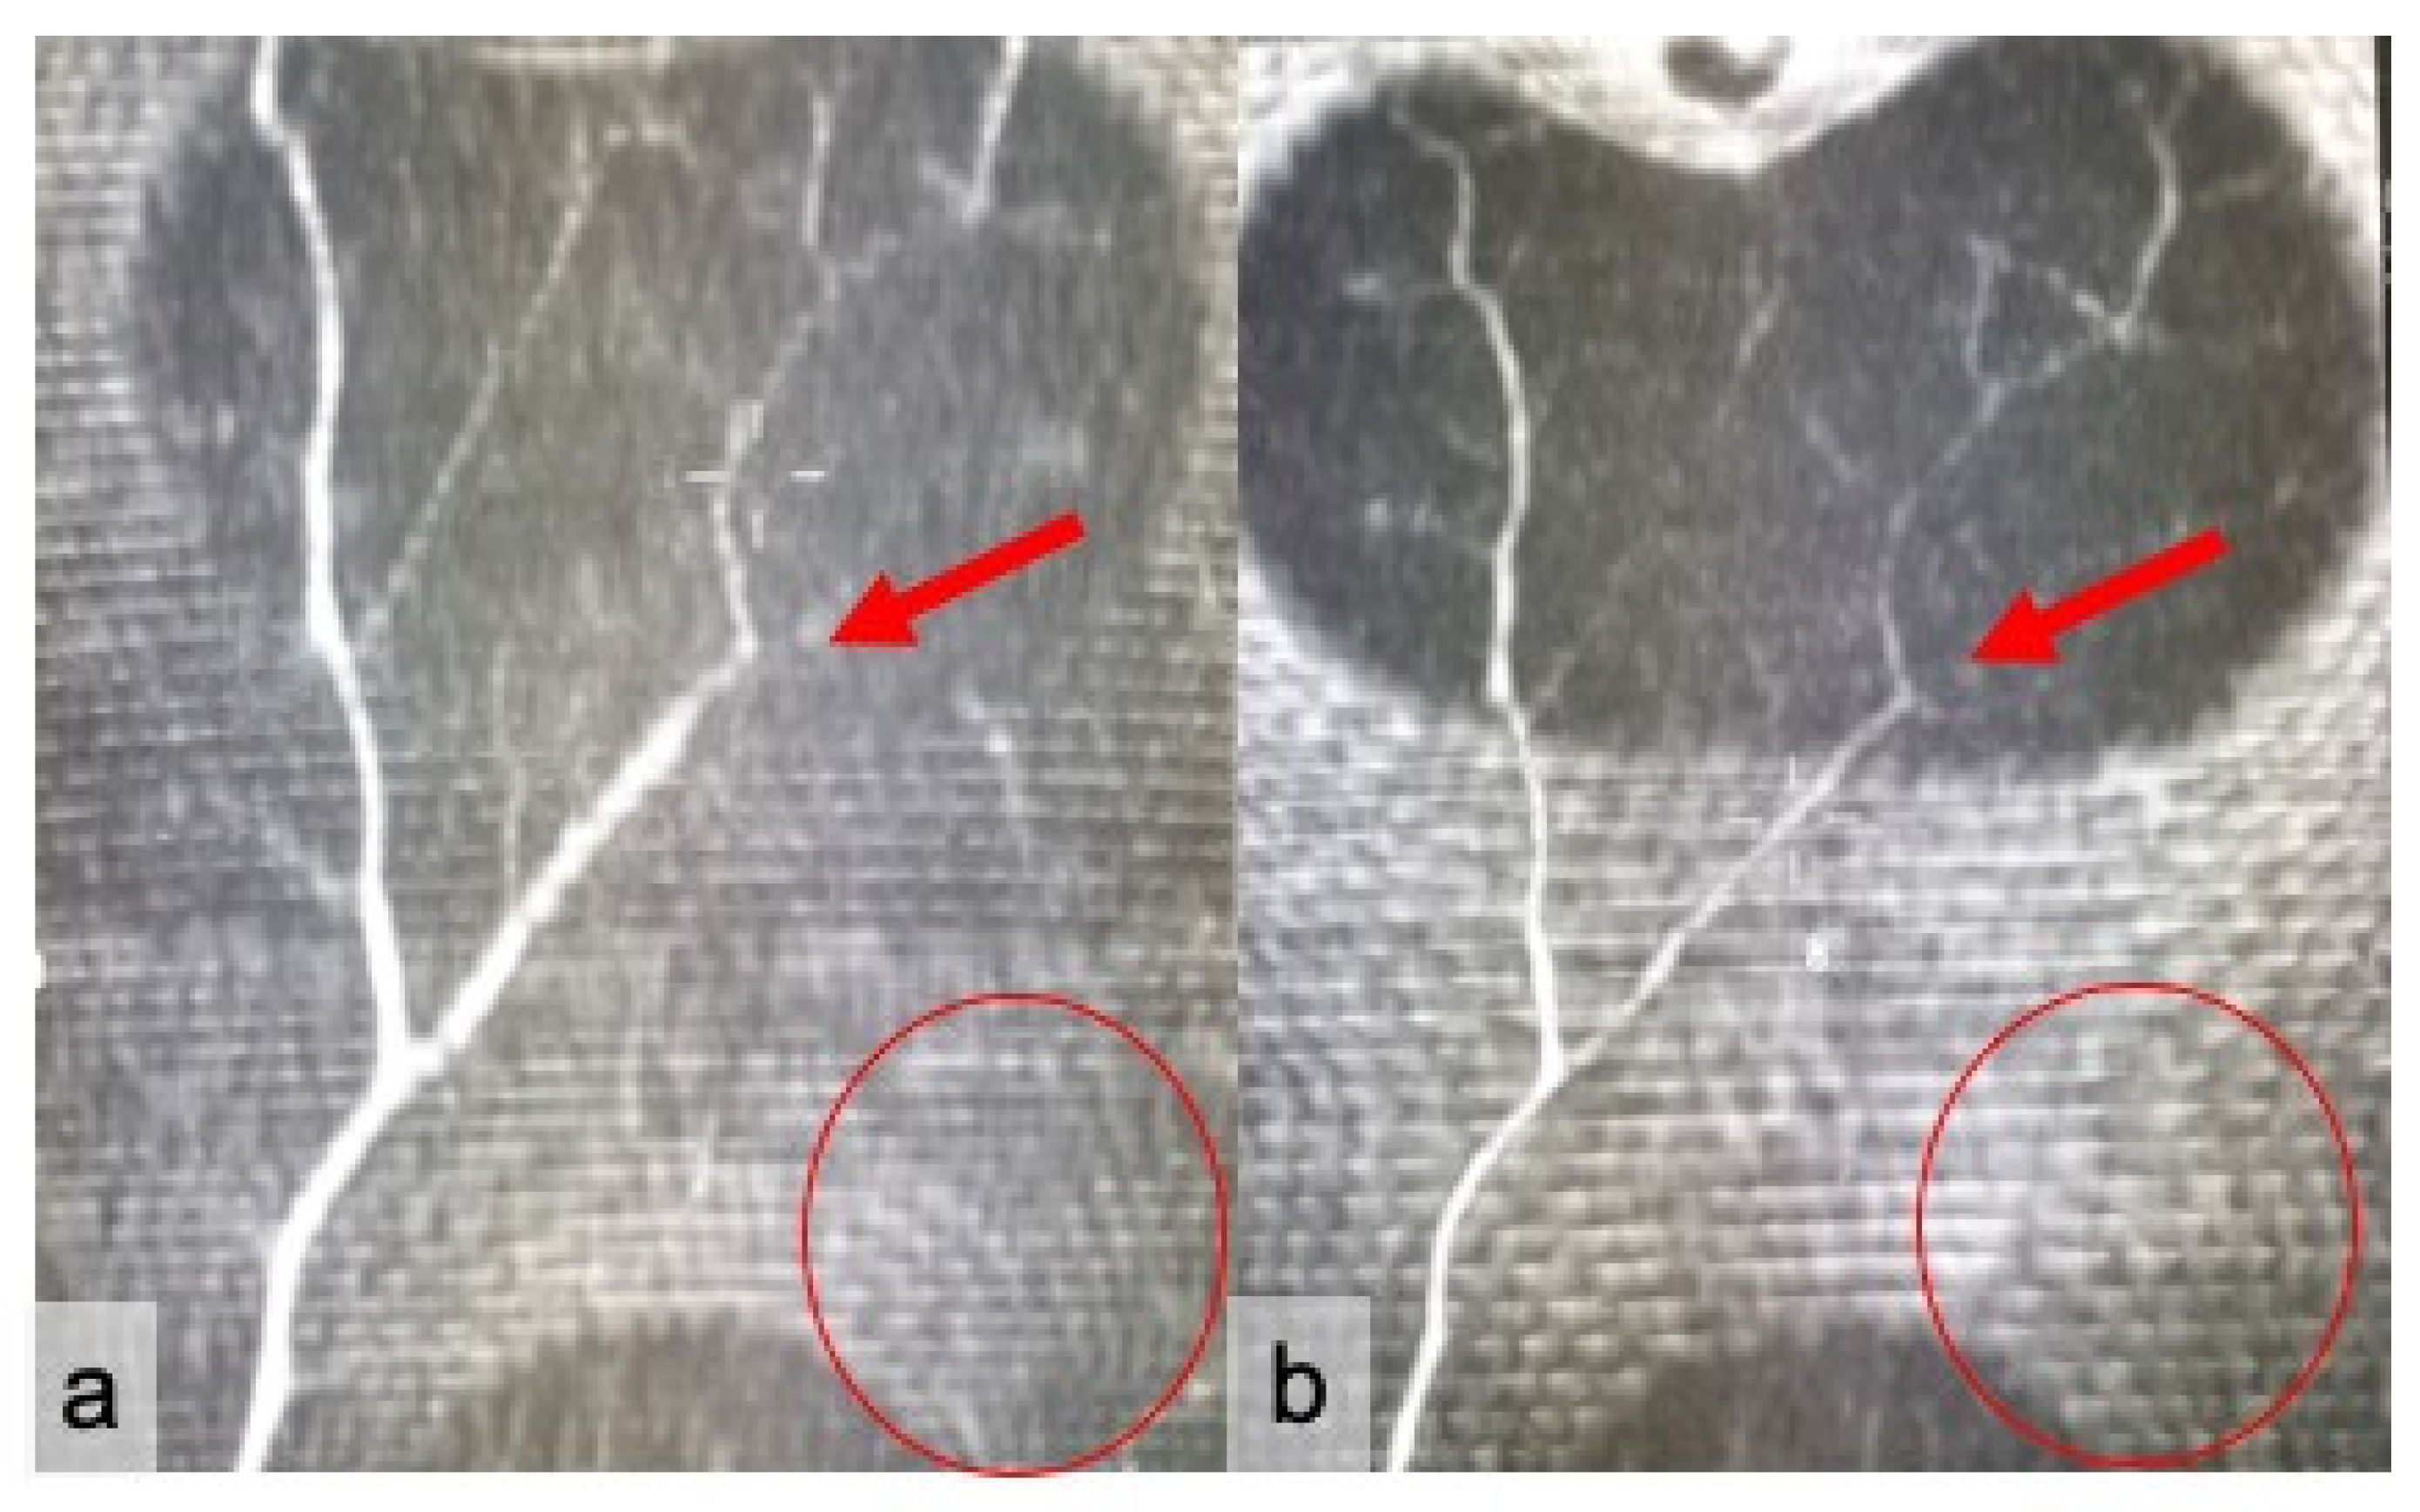

2.2. Image Analysis

3. Results